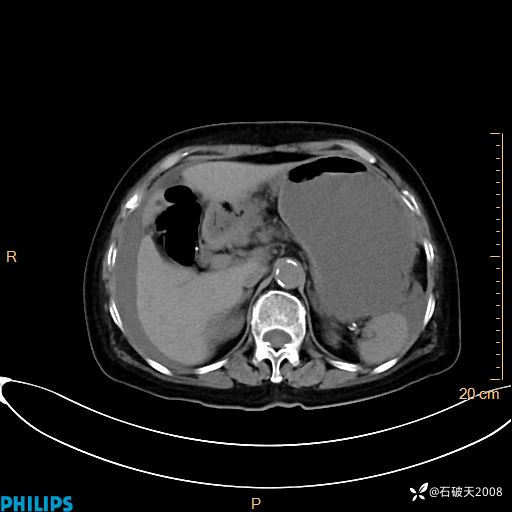

静脉期